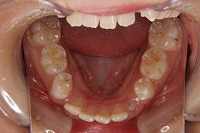

反対咬合を主訴に来院された、右側唇顎裂の10歳6ヵ月の女の子です。診断「右側唇顎口蓋裂で反対咬合を伴う」1期治療で反対咬合の解消と上顎の前歯の並びを修正しました。2期治療は抜歯をせず治療を行いました。